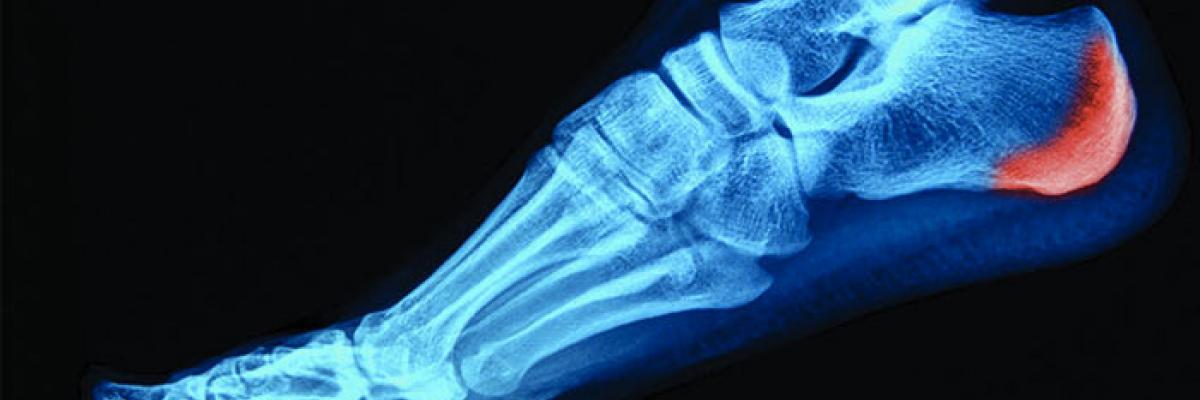

El espolón calcáneo se trata de un osteofito el cual crece en la región anterior de la tuberosidad plantar del calcáneo y que se extiende en sentido posteroanterior de 1 a 2 cm, su extremo anterior interrumpe en la fascia plantar como una espina calcánea con densidad ósea, el cual puede ser de diferentes formas y tamaños pero generalmente es triangular.

Un 45% de los pacientes con la fascitis plantar pueden presentar espolón, el hecho de presentar un espolón no es indicativo de presentar fascitis plantar debido a que la mayoría de los espolones no resultan dolorosos y son descubiertos de manera accidental a través de radiografías, no obstante, están presentes el 50% de las talalgias. En estudios en pacientes con fascitis plantar se ha demostrado que del 10 al 70% pueden presentar espolón calcáneo asociado, si bien la mayoría presenta también un espolón en el pie asintomático contralateral.